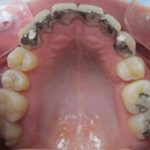

Arcade mandibulaire avant traitement orthodontique, séquelles de maladie parodontale

Après traitement orthodontique et réalisation d’une attelle fibrée (courtoisie Dr Patrick Fournier)